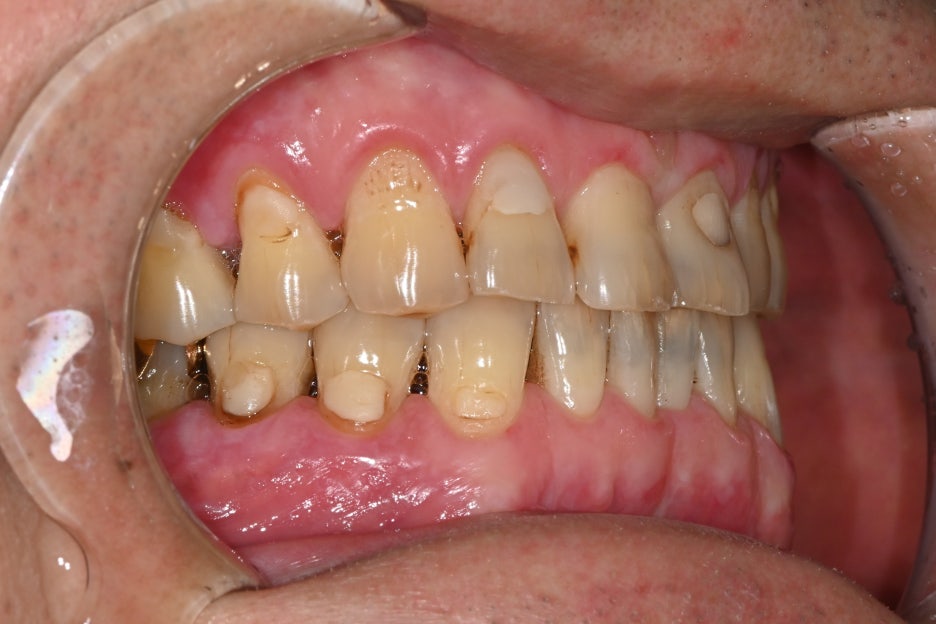

안녕하세요! 서울오브치과병원입니다. 오늘은 왼쪽 아래 어금니 임플란트 수술 사례를 소개해드리겠습니다. 환자분은 오래 전 발치 후 방치해 두었던 자리 때문에 씹는 불편함이 생겨 치료를 원하셨습니다. 초진 내원 당시 왼쪽 아래 어금니를 예전에 뽑았는데 요즘은 반대쪽으로만 씹다 보니 턱도 불편해요 환자분은 “왼쪽...

환자분은 오래 전 발치 후 방치해 두었던 자리 때문에

씹는 불편함이 생겨 치료를 원하셨습니다.

초진 내원 당시

왼쪽 아래

어금니를 예전에 뽑았는데

요즘은 반대쪽으로만 씹다 보니

턱도 불편해요

환자분은 “왼쪽 아래

요즘은 반대쪽으로만 씹다 보니 턱도 불편하다”는

주호소로 내원하셨습니다.

치아가 오랫동안 결손된 상태라 양쪽 균형이 맞지 않고

음식물이 자주 끼면서 잇몸도 불편했다고 말씀하셨습니다.